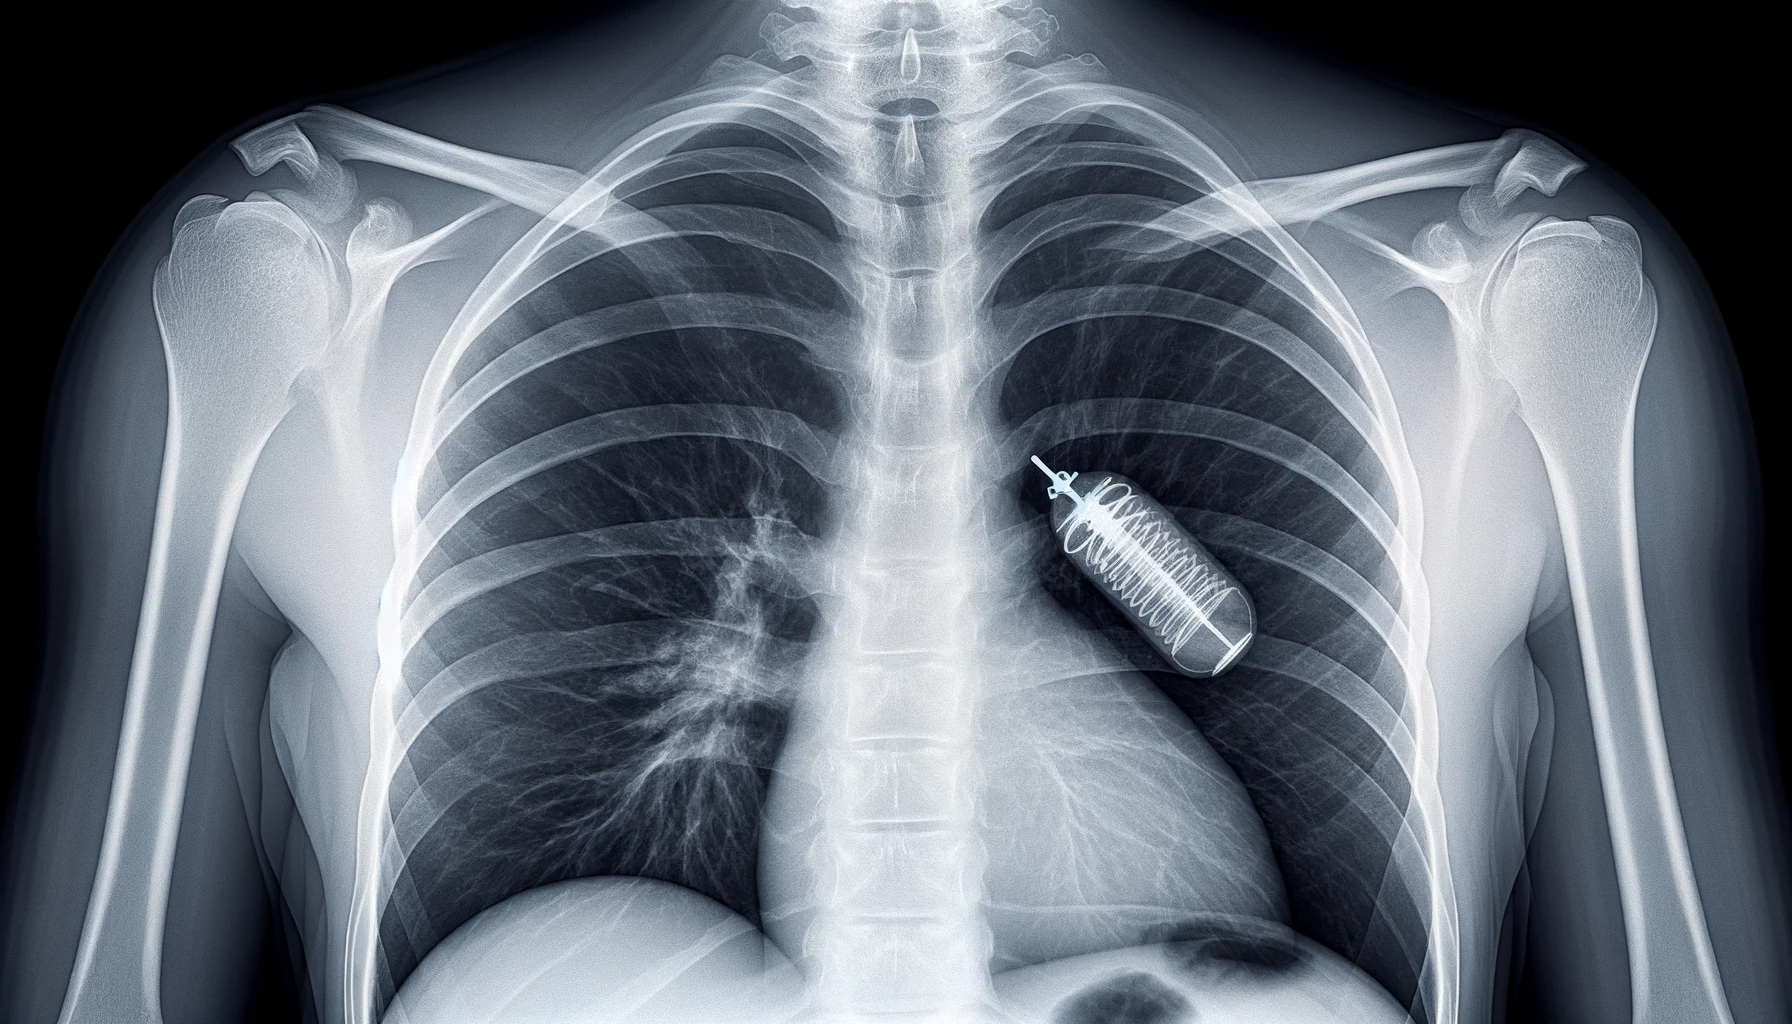

Хирургический ящик Пандоры. Врачи рассказали о самых странных находках внутри людей

Хотя извлечение инородных предметов из тел людей уже является нормой для множества хирургов, некоторые из извлеченных предметов смогли бы поразить даже повидавших многое врачей. focus.ua »